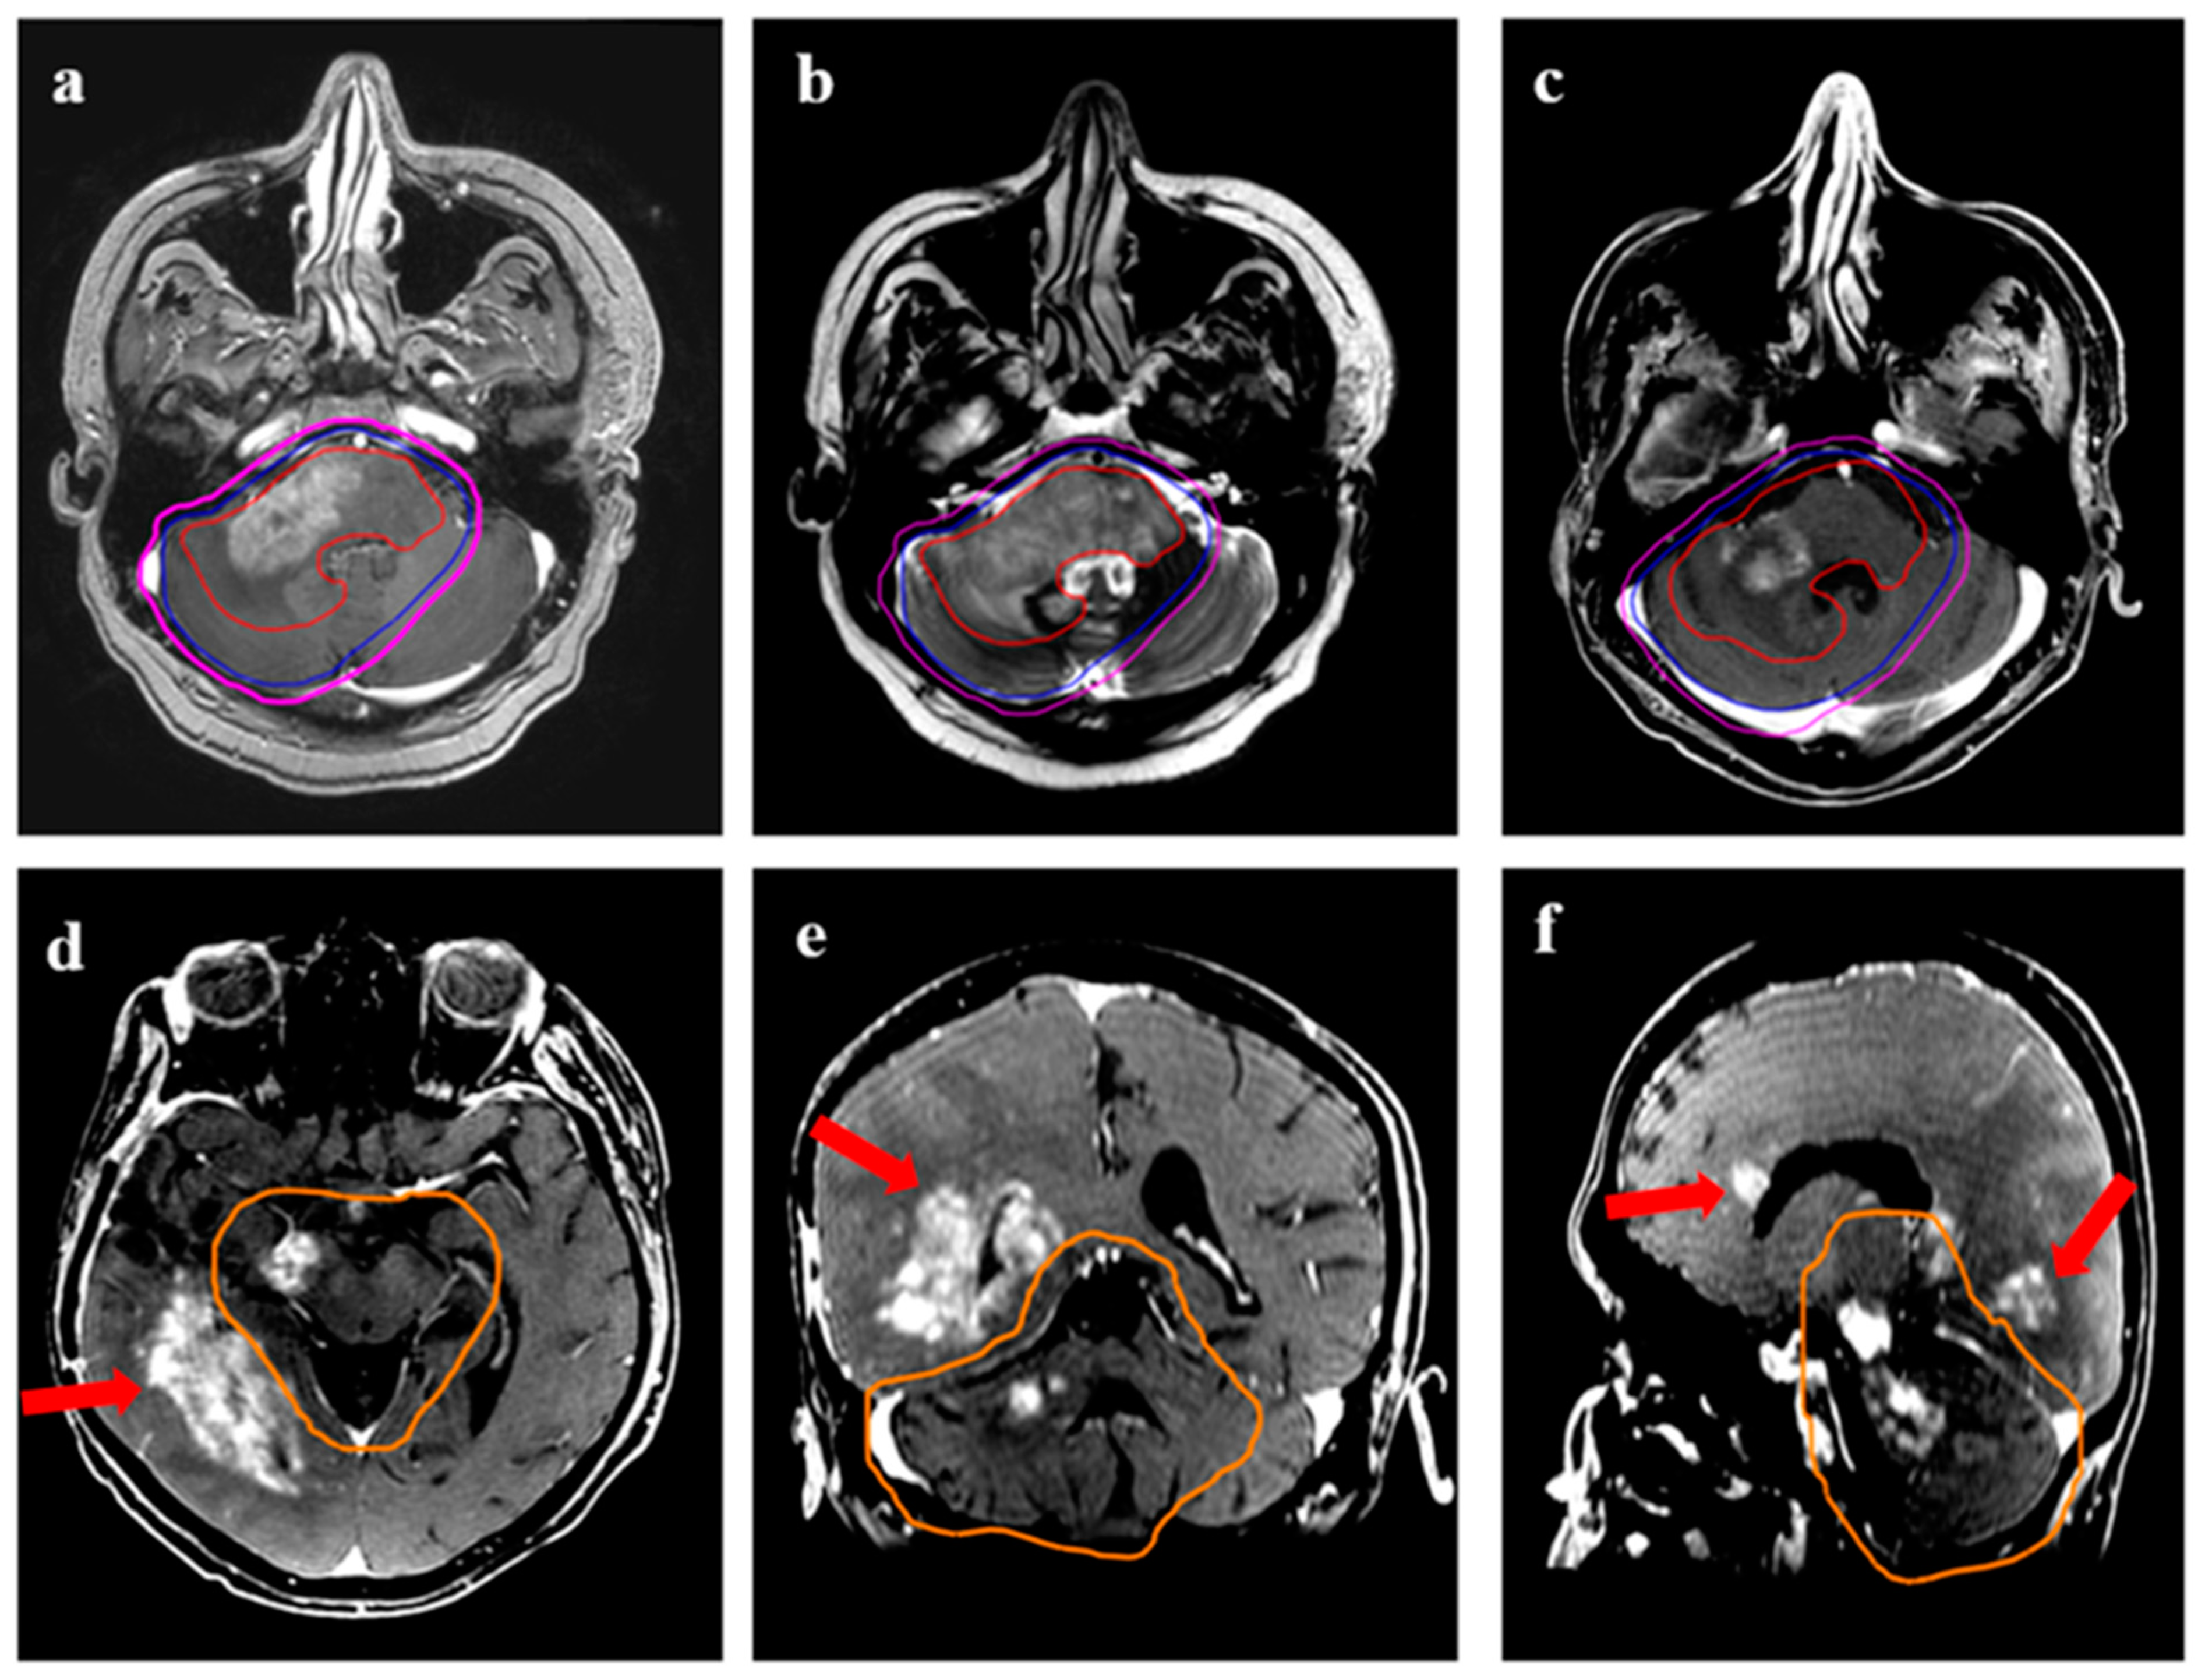

| Patterns of recurrence (with respect to 95% isodose) | |

| Central | 27 (73%) |

| Marginal | 4 (11%) |

| Distant | 6 (16%) |

| Time to recurrence after re-irradiation | |

| Median (range) | 9 (1–47) months |

| Volume of recurrence following re-irradiation | |

| Median (range) | 69.5 (3.3–221) cc |